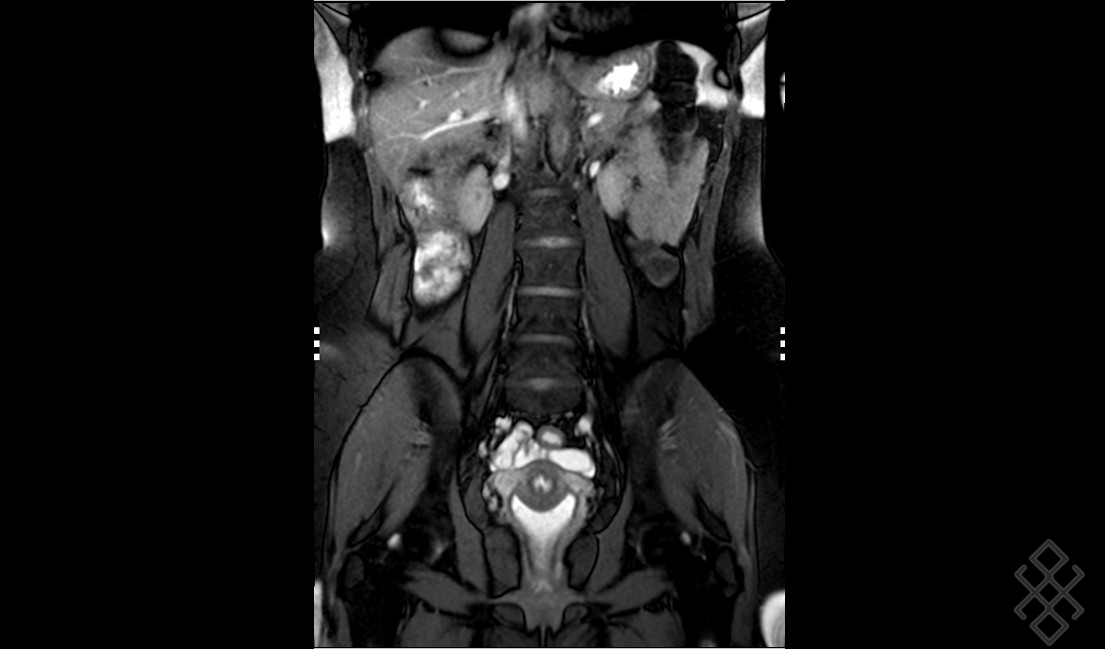

IRM pelvienne L'IRM est un examen non irradiant, sans risque, qui est très utile pour le diagnostic et le bilan d'une endométriose puis Comment se déroule l'examen IRM pelvienne dynamique ?

Dans la plupart des cas d'IRM pelvienne, vous devrez faire un lavement évacuateur quelques heures avant l'examen Comment faire un lavement Evacuateur ? Un lavement évacuateur consiste à injecter par l'anus un liquide dans le rectum ou l'extrémité du. Une préparation digestive par lavement rectal (Microlax) est recommandée afin d'améliorer la qualité des images.

MA 1ERE IRM PELVIENNE ENDOMETRIOSE YouTube. Il est conseillé de réaliser un lavement rectal à domicile au Normacol, idéalement 1 à 3h avant l'examen si possible du Microlax et éventuellement du produit de contraste gadoliné en fonction de l'indication de l'IRM pelvienne.